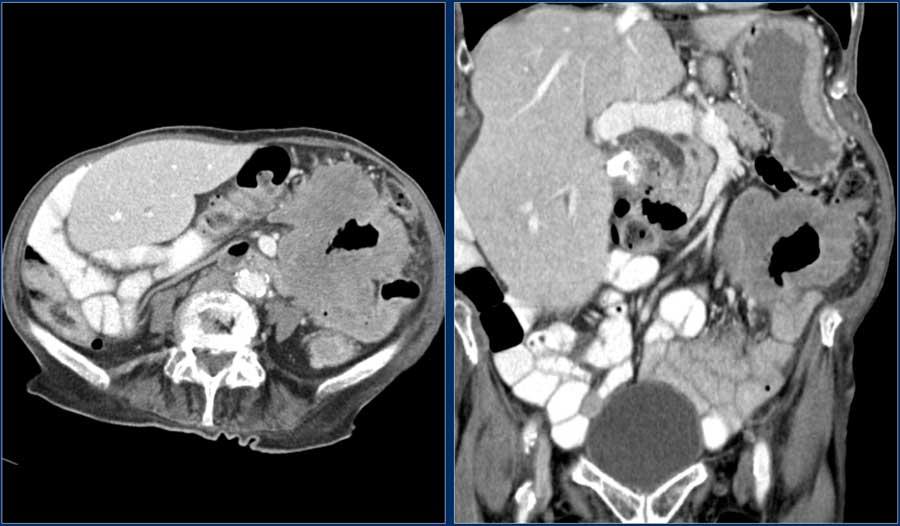

Hãy quan sát ảnh CT tái tạo mặt phẳng coronal.

Sau đó tiếp tục đọc.

Các dấu hiệu hình ảnh:

- Tổn thương hẹp lòng tá tràng do ung thư biểu mô tuyến (mũi tên vàng).

- Không thể phân tách khỏi tụy (mũi tên đỏ).

- Giãn tá tràng trước chỗ hẹp.